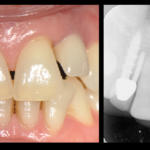

Home L’estetica degli impianti “one piece” di scuola italiana a carico immediato nei settori frontali Fig. 5 Terzo caso clinico. L’agenesia dei laterali superiori risolta dopo ortodonzia con 2 mini impianti a vite M.U.M. e ago di stabilizzazione sincristallizzato (1988).